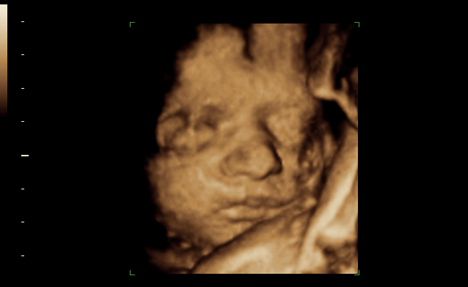

large151209.jpgY a-t-il quelque chose de plus intime que ses propres entrailles? Un enfant dans le ventre de sa mère a-t-il un droit sur l’utilisation de son image publique? La diffusion, de plus en plus courante, des images d’échographies sur internet — par e-mail généralisé ou sur des profils Facebook — franchit une nouvelle étape dans l’exposition publique d’une dimension particulièrement privée de la vie d’une future mère et d’un couple.

Les progrès dans l’utilisation des ultrasons ont aussi dopé le phénomène. «Avec l’échographie tridimensionnelle, on n’obtient plus un profil mais quasiment une photo du visage de l’enfant», relève Yvan Vial, médecin chef du service d’obstétrique et responsable de l’unité d’échographie du CHUV. L’échographie reste un outil diagnostique, mais si l’enfant est bien positionné, le résultat devient photogénique et particulièrement émouvant. «Notre société valorise tellement l’image, n’est-il pas logique que les futurs parents veuillent partager celles qu’ils ont de leur bébé?», interroge le spécialiste.